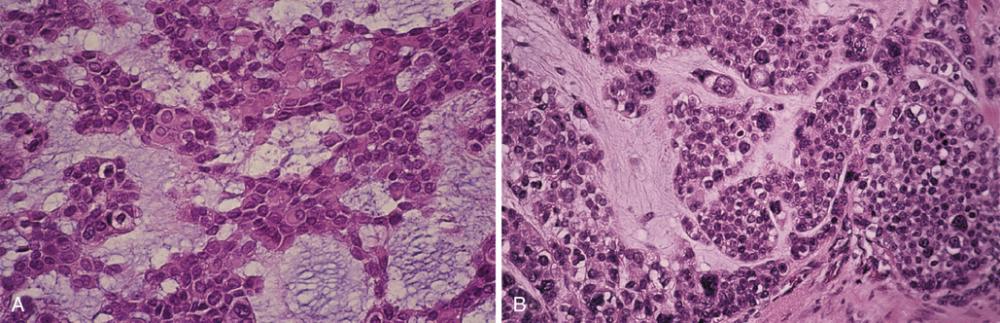

- A, Medium-power view of the benign portion of the tumor showing sheets of plasmacytoid myoepithelial cells within a myxoid background.

- Malignant portion of the tumor showing epithelial cells with pleomorphic nuclei.

carcinoma ex pleomorphic adenoma